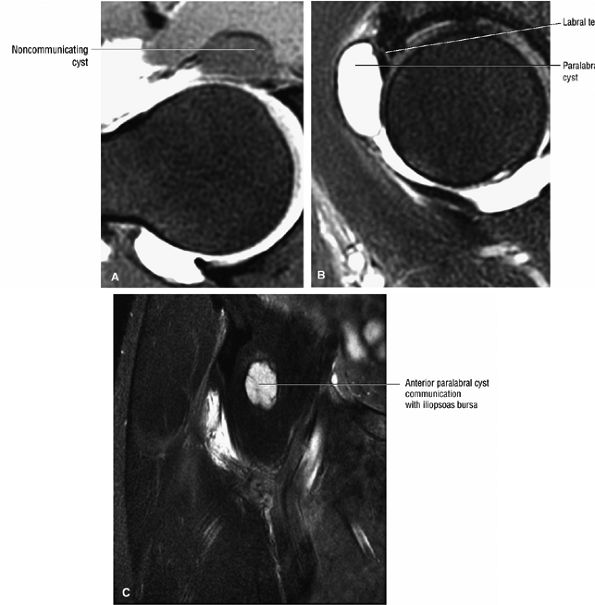

FIGURE 3.29 ● Normal axial anatomy of the hip. (A, B) At this level, the sciatic nerve can be seen exiting the sciatic foramen, deep to the piriformis muscle. Asymmetric enlargement of the piriformis muscle or masses in this region can cause impingement of the sciatic nerve, the so-called piriformis syndrome. (C, D) At this level the transition from the acetabular roof to the top of the femoral head is visualized. The thin arc of dark signal along the lateral margin of the acetabular roof represents the superior margin of the labrum. High signal in the superior labrum can be identified as a labral tear, and accompanying paralabral cysts are commonly identified extending superficial to the labrum. (E, F) The anterior labrum and the posterior labrum on axial images are identified as dark-signal triangles at the lateral margin of the acetabuli. Labral tears present as linear or irregular fluid signal extending through the substance of the labrum, or as expansion of the labrum by fluid signal extending to the surface of the labrum. Fluid signal interposed between the labrum and the acetabulum at the labral attachment indicates labral detachment.(G, H) Tendinosis of the gluteus medius and minimus insertions on the greater trochanter is visualized as thickening and increased signal of the tendons. Trochanteric bursitis can be identified either superficial or deep to the gluteus medius and minimus insertions. (I, J) A fluid collection anteromedial or anterolateral (or both) to the iliopsoas tendon is compatible with iliopsoas bursitis. Occasionally, iliopsoas bursitis may be present adjacent to an anterior labral tear, in which case it may be difficult to distinguish from a paralabral cyst. (K, L) The common hamstring origin on the ischium comprises the biceps femoris and semitendinosus tendons. The common hamstring tendon is a frequent site for tendinosis or partial tears, and the pathology is commonly symmetric.